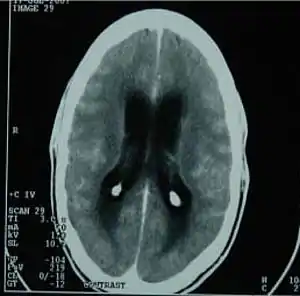

![]() Ознаки туберкульозного менінгіту на комп'ютерній томографії мозку Ознаки туберкульозного менінгіту на комп'ютерній томографії мозку | |